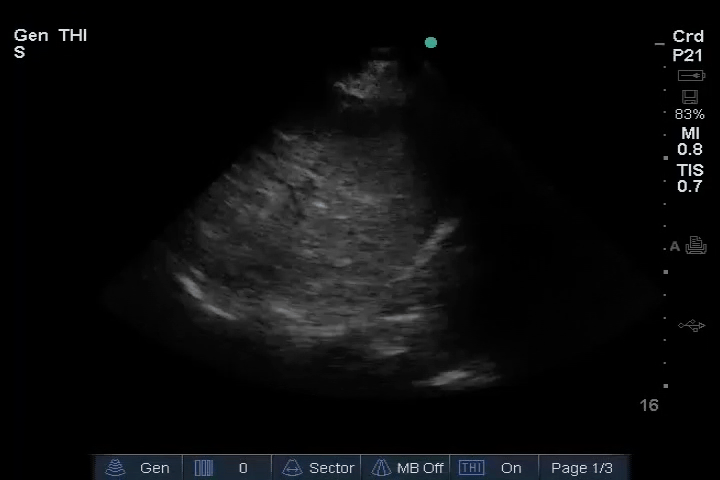

10_Heart_SC – LV reduced ejection fraction (EF)